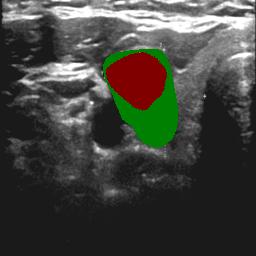

3.3 High-confidence Multi-level labels Generation

According to Reference 1 and Reference 2 discussed in Sec. 3.2, weakly supervised segmentation requires nodule location labels for location learning and region distribution labels for shape learning. In this section, we integrate geometric transformations of point annotations and segmentation from prompted MedSAM to generate high-confidence location labels for location learning in Eq. (1), as well as high-confidence foreground labels and background labels for shape learning in Eq. (2) and Eq. (3).

Specifically, as illustrated in Fig. 1, in the high-confidence labels generation phase, we derive three geometric transformations representing low-level topological information from clinical annotations:

Connecting the endpoints of the annotations along each axis to form quadrilateral regions.

Identifying and filling the minimum bounding box enclosing these four points per target to create box regions encompassing all foreground pixels.

Negating the bounding box regions results in obtaining background-only regions.

The regions that contain high-level semantic information are generated by prompted MedSAM:

Using MedSAM with prompts computed from point annotations to obtain segmentation masks that reflect anatomical distributions from input images.

Finally, we fuse the initial topological shape ex-rectangle , in-quadrilateral , and out-rectangle and results from prompted MedSAM to generate high-confidence location , foreground , and background labels .

| (4) | ||||

where denotes the logical OR operation applied to the positions of two masks, while represents the logical AND operation.

As shown in Table 1, the comparison of different pseudo-labels as supervision references in terms of precision, which is the ratio of correct pixel categories in pseudo-label pixels, showed that the proposed high-confidence labels can provide more reliable reference information. When high-confidence foreground/background labels served as supervision references to learn the foreground and background, they achieved higher precision (over 99.66% for foreground and 99.98% for background) than those obtained using solely topological geometric transformation (no more than 98.65% for foreground) and MedSAM results (no more than 97.11% for foreground and 97.85% for background). In two datasets, our generation of high-confidence foreground and background labels achieved precision exceeding 99.66% across domain distributions.

The region reference precision of high-confidence labels is parallel to 100% because we combine geometric topological transformation with topology priors and MedSAM prediction with anatomical information, further reducing areas of uncertainty. Therefore, they can serve as foreground and background reference and without misleading network learning, as outlined in Sec. 3.2